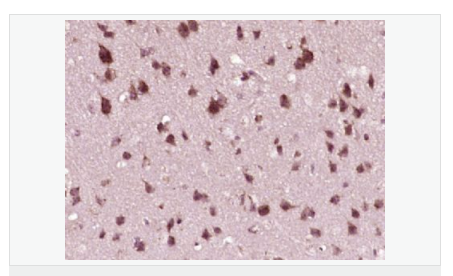

| 產品應用 | WB=1:500-2000 ELISA=1:5000-10000 IHC-P=1:100-500 IHC-F=1:100-500 Flow-Cyt=1ug/test ICC=1:100-500 IF=1:50-200 (石蠟切片需做抗原修復) not yet tested in other applications. optimal dilutions/concentrations should be determined by the end user. |

| 細胞定位 | 細胞核 細胞漿 |